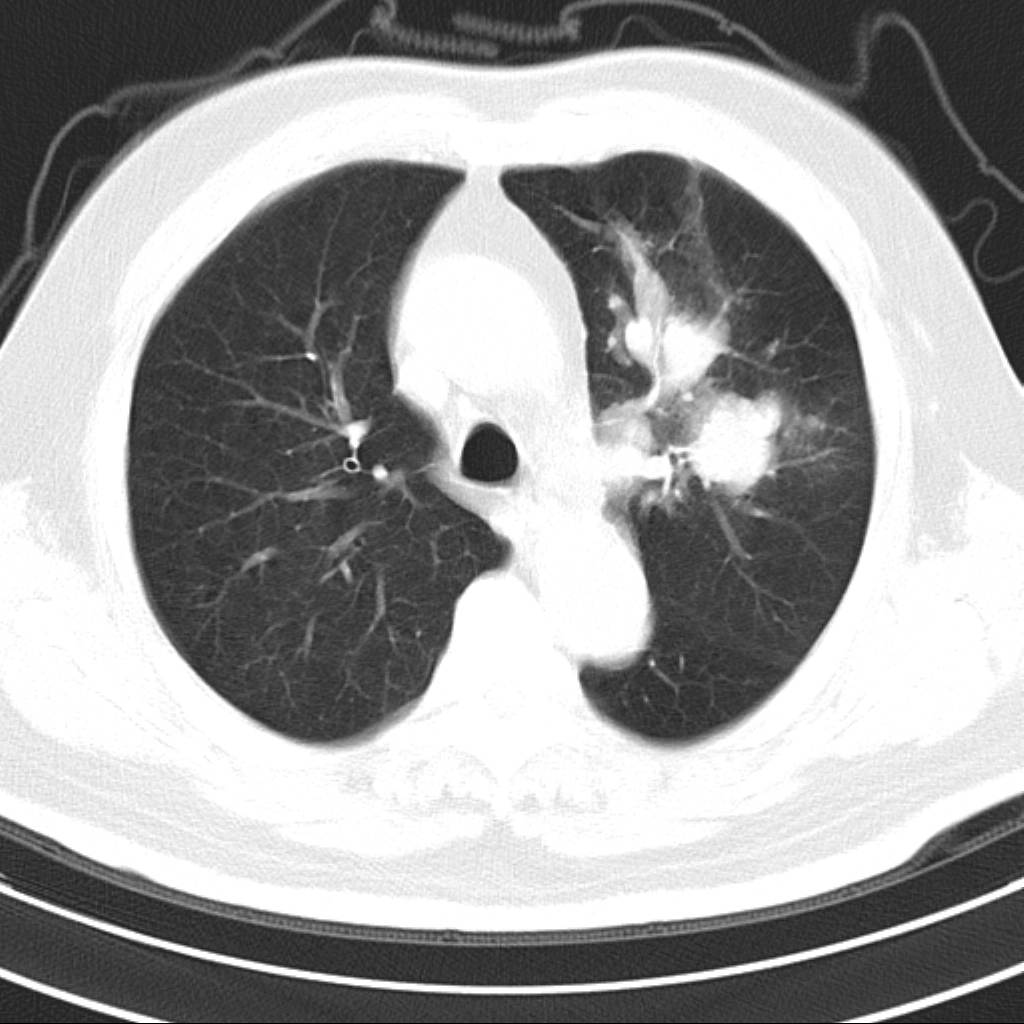

标题: CT18644:男,82岁,体检发现左肺阴影. [打印本页]

标题: CT18644:男,82岁,体检发现左肺阴影.

岁数太大,没有增强。麻烦见过的,给个诊断,顺便再说说病因

左侧中心型肺癌并粘液栓形成。很典型的。手套征。

支持 左肺上叶中央型肺癌并支气管内粘液栓形成。

支持考支气管扩张伴粘液栓,但导致粘粘液栓的病因有待进一步检查。支持左上叶支气管基部肿物,肺癌可能性大,但肿块似与肺动脉右支保持良好的伙伴关系,不除外为肺动脉扩张所致,建议增强。

尚不除外非感染炎症,过敏及哮喘曲霉菌病所致黏液栓塞,纸套征比较形象妾有一定特异性

考虑左肺上叶中央型肺癌并支气管内粘液栓形成。

支持 左肺上叶中央型肺癌并支气管内粘液栓形成,阻塞性肺炎

考虎左肺上叶中央型肺癌并支气管内黏液栓形成,不能增强是个遗憾,期待复查结果。